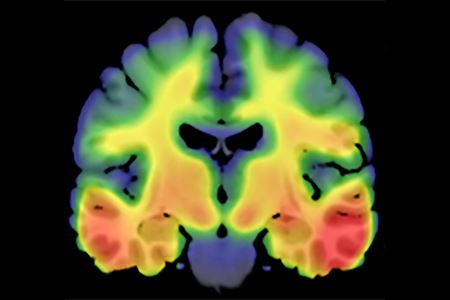

Image of a brain slice illuminated in rainbow colors

While previous studies have made strides in identifying genetic variants associated with amyloid deposition, understanding the genetic drivers of tau deposition has been more challenging. This study helps fill that gap in understanding, the researchers said. | Image courtesy of Shannon Risacher